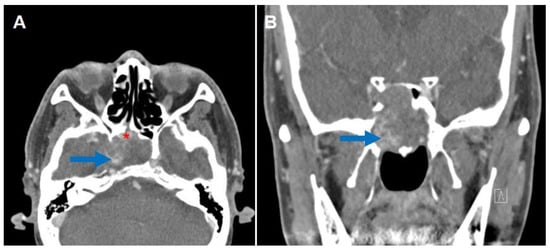

2. Case Report